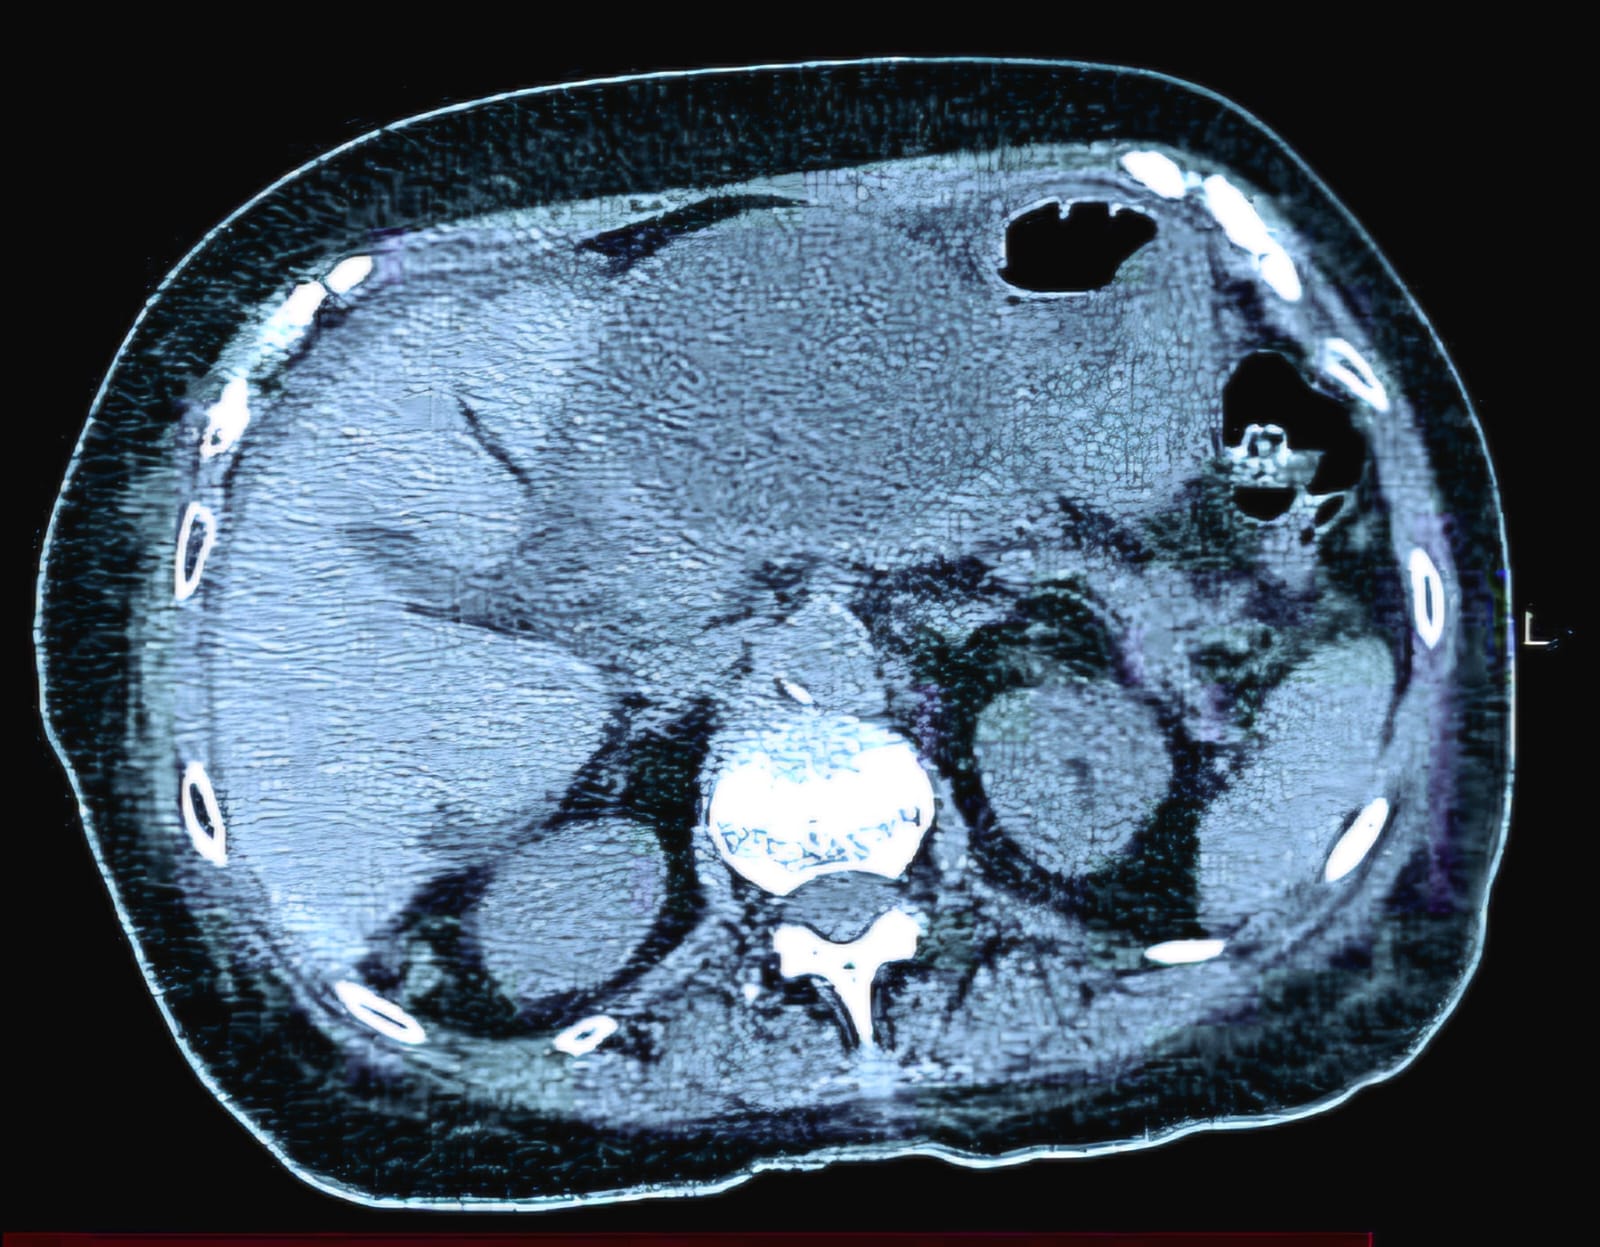

La paciente, una mujer de 83 años proveniente del departamento de Itapúa, presentaba un quiste que se formó luego de una inflamación del páncreas y que le dificultaba la alimentación, ya que presionaba el estómago. Ante esta situación, el equipo médico decidió realizar un tratamiento menos invasivo, utilizando un endoscopio.

El Dr. Félix Ibieta Galarza explicó que el procedimiento consistió en crear una pequeña comunicación interna para drenar el líquido acumulado en el quiste, lo que permitió aliviar la presión y mejorar los síntomas de la paciente. Para ello, se colocaron pequeños dispositivos que facilitan el drenaje de forma segura.